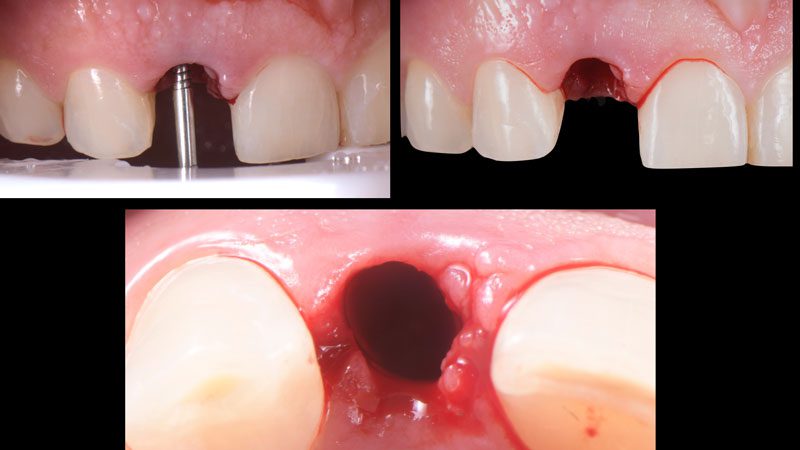

Bài viết dưới đây sẽ dẫn chúng ta đến với 1 ca lâm sàng cắm Implant tức thì răng cửa bên hàm trên. Implant được chỉ định vì thân răng bị gãy quá sâu dưới nướu, cấu trúc răng còn lại không đủ để thực hiện phục hồi.

Hình 9. 3 tháng sau khi cắm Implant, chú ý cấu trúc mô mềm xung quanh vẫn còn nguyên.

Hình 10. Lấy dấu bằng coping cá nhân để ghi lại cấu trúc mô mềm và chuyển qua mẫu hàm cho chính xác.

Hình 11. Phục hình tạm lưu giữ bằng ốc vặn.